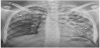

Figures 1, 2 and 3 are photographs of children of the series, respectively showing chest X-ray, fistulized lymphadenopathy, and spinal gibbosity.

- a vast cavern of the lingula (star) with a drainage bronchus (double arrow)

- a right apical infiltrate (arrow)

- and a left basal milial aspect (arrowhead).

Chest X-ray was abnormal in 21 children. Pulmonary lesions were varied and dominated by parenchymal infiltrates. Cellular condensation was found in 32.1% of patients. Four cases of military radiological were observed. Table 3 illustrates the different lesions and their frequencies.